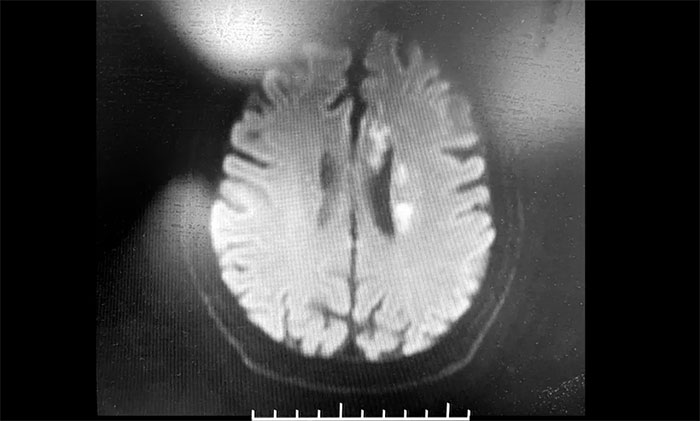

神经内科3A病区周君主任详细了解病史,查体,并为韩老伯完善相关的检查。头颅MRI示:脑干及双侧大脑半球多发陈旧梗死灶,左侧胼胝体、半卵圆中心、侧脑室旁及额叶多发梗死灶,偏亚急性期。脑动脉硬化,颅底动脉多发不同程度狭窄(左侧颈内虹吸段为著)。

▲ 头颅MRI示:左侧多发梗死灶,左侧颈内动脉狭窄

周君主任表示,从影像学上,患者左侧脑室旁散在多个新鲜梗死灶,呈比较典型的“分水岭样梗塞”表现。分水岭样梗塞(Watershed infarction,WI),是指发生在脑部两条主要动脉分布区的交界处的脑梗死,多发生于脑部较大动脉供血交界区。

韩老伯的新发病灶处在左侧颈动脉供血支配范围内,符合因左侧颈内动脉狭窄而造成脑组织缺血表现,需要针对这一引起脑梗的病因,及时采取干预治疗措施。